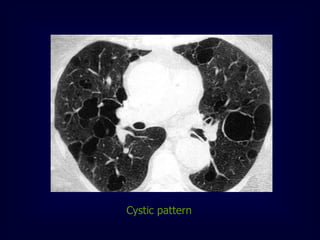

Cystic pattern

[ multiple thin walled air containing lesions 1cm or more ]

Histeocytosis

Lymphangioleiomyomatosis

Lymphocytic interstitial pneumonia

Emphysema

Cystic bronchiectasis

Tuberous sclerosis

Cystic pattern [ multiplethin walled air containing lesions 1cm or more ] Histeocytosis Lymphangioleiomyomatosis Lymphocytic interstitial pneumonia Emphysema Cystic bronchiectasis Tuberous sclerosis